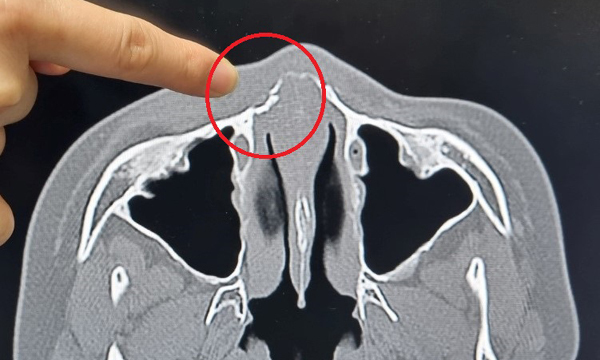

병원에서 컴퓨터 단층(CT)촬영을 한 결과 B군 코뼈가 부러졌다는 진단을 받았다.